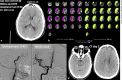

Background: Determining the size of infarct extent is crucial to elect patients for reperfusion therapies. Computed tomography perfusion (CTP) based on cerebral blood volume may overestimate infarct core on admission and consequently include ghost infarct core (GIC) in a definitive lesional area.

Purpose: Our goal was to confirm and better characterize the GIC phenomenon using CTP cerebral blood flow (CBF) as the reference parameter to determine infarct core.

Methods: We performed a retrospective, single-center analysis of consecutive thrombectomies of middle cerebral or intracranial internal carotid artery occlusions considering noncontrast CT Alberta Stroke Program Early CT Score ≥6 in patients with pretreatment CTP. We used the RAPID® software to measure admission infarct core based on initial CBF. The final infarct was extracted from follow-up CT. GIC was defined as initial core minus final infarct > 10 mL.

Results: A total of 123 patients were included. The median National Institutes of Health Stroke Scale score was 18 (13-20), the median time from symptoms to CTP was 188 (67-288) min, and the recanalization rate (Thrombolysis in Cerebral Infarction score 2b, 2c, or 3) was 83%. Twenty patients (16%) presented with GIC. GIC was associated with shorter time to recanalization (150 [105-291] vs. 255 [163-367] min, p = 0.05) and larger initial CBF core volume (38 [26-59] vs. 6 [0-27] mL, p < 0.001). An adjusted logistic regression model identified time to recanalization < 302 min (OR 4.598, 95% CI 1.143-18.495, p = 0.032) and initial infarct volume (OR 1.01, 95% CI 1.001-1.019, p = 0.032) as independent predictors of GIC. At 24 h, clinical improvement was more frequent in patients with GIC (80 vs. 49%, p = 0.01).

Conclusions: CTP CBF < 30% may overestimate infarct core volume, especially in patients imaged in the very early time window and with fast complete reperfusion. Therefore, the CTP CBF technique may exclude patients who would benefit from endovascular treatment.